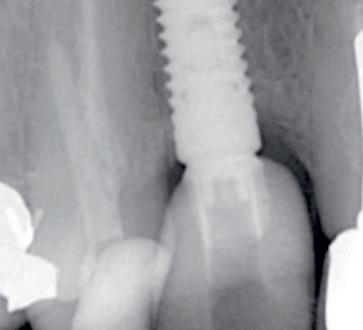

Een 62-jarige man hield in de nazorgfase een pocket van 8 mm met bloeding na sonderen mesiaal van de 36 ondanks 3-maandelijkse recall (afbeelding 2.1 en 2.3). De mondhygiëne was matig en plaque was aanwezig. Chirurgie werd geadviseerd, maar de pa-

tiënt wees dit af. Ook hier werd de pocket behandeld onder anaesthesie. De natriumhypochloriet/aminozuur-gel werd viermaal aangebracht, telkens gevolgd door ultrasone en handinstrumentatie. Tot slot werd cross-linked hyaluronzuur ingebracht. De mondhygiëne werd bijgestuurd en meneer werd gemotiveerd dagelijks interdentale ragers te gebruiken naast het poetsen.

Na zes maanden was de pocketdiepte teruggebracht tot 3 mm en was er geen bloeding na sonderen (afbeelding 2.2 en 2.4).